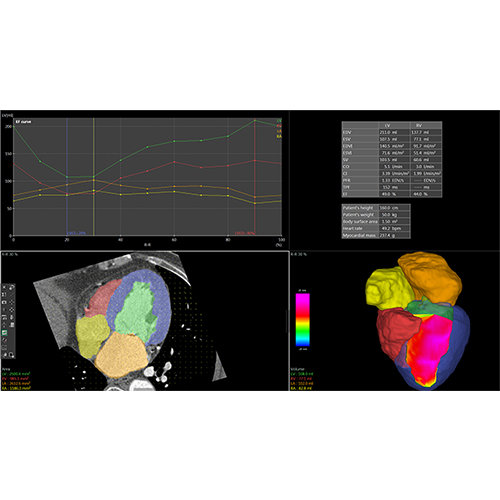

View X-Ray CT & MRI Scans Fast and Easily

Designed for surgeons, Pro Surgical 3D makes it easy to view patient scans quickly. Pro Surgical 3D facilitates the optimal 3D treatment and assessment workflows based on X-ray CT and MRI scans – and best of all, it’s FREE!

High-quality and fast 3D reconstruction and 3D rendering

Performs 3D reconstruction and volume rendering.